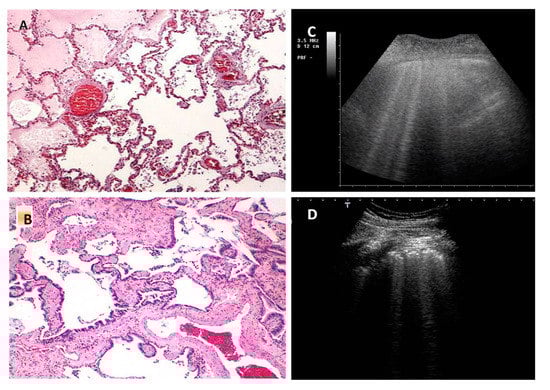

Figure 4.

(A): The picture represents a pulmonary scan of a newborn with Hyaline membrane disease, showing White lung (Image obtained with a commercially available machine, Esaote MyLab 25 equipped with a linear probe 10 MHz). On the right (B) the corresponding histopathological picture. Residual airspaces are small (about 50 μm), separated by a mean distance in the order of 100–150 μm. In this condition the small diameter of the scattering bubbles and their small relative distance are probably the prerequisites for this acoustic effect.

The White Lung pattern suggests the presence of a relatively homogeneous scatterer distribution (many small airspaces close to each other which contribute to the formation of many small acoustic traps) which gives rise to numerous multiple reflections. A random distribution of small and close scattering air bubbles is needed to obtain such a pattern [33]. In this case, the expected histology is consistent with a diffuse pathological reduction of the air spaces which, however, would remain surrounded by enough interstitium to allow the type of interaction just described. In white lung, the distribution of the scatterers does not deny the existence of a relatively ordered porous structure.